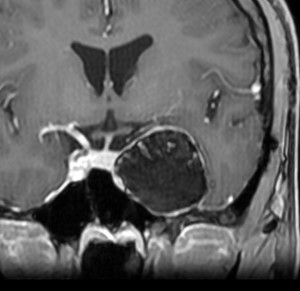

7歳の時に偶然発見された左海綿静脈洞外壁の類皮のう胞 dermoid cystで,多数の脳神経と皮膜が癒着するものです。この腫瘍は先天性の腫瘍なのでおそらく生まれた時からあったものです。10歳の時に手術摘出しました。画像は22歳の時の手術前のものです。何故2回も部分摘出したのかは,この類皮のう胞というのは脳組織や髄膜や脳神経にベトベト癒着してくっつく性質があるからです。海綿静脈洞内にある脳神経と剥離できませんでした。でも初回手術から12年無症状でしたし,2回目の手術後も無症状です。

左側の画像はガドリニウム増強のT1強調MRIです。壁が厚いと造影剤で増強されることがありますが,この壁はとて硬いです。